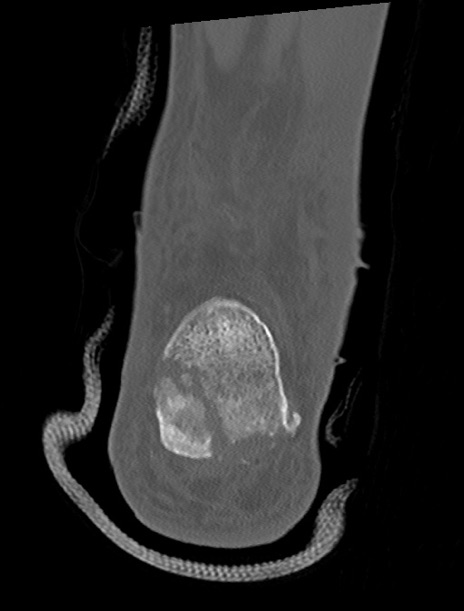

症例37 左足関節CT(冠状断像)

左足関節CT

横断像